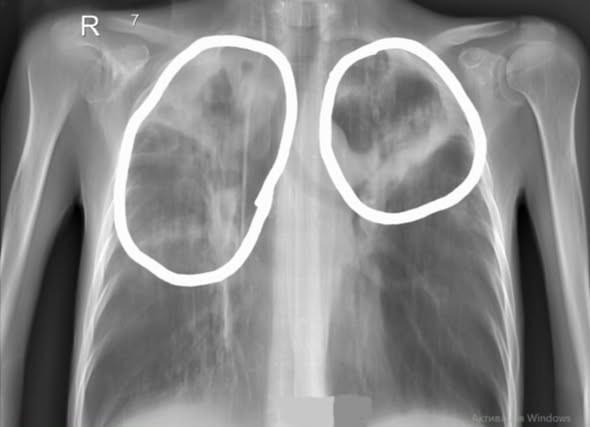

В Центр фтизиопульмонологии г. Алматы поступила пациентка Л. 42 лет в тяжёлом состоянии. При поступлении был диагностирован рецидив туберкулёза с запущенной формой заболевания - казеозная пневмония с бактериовыделением, выраженная кахексия, дыхательная недостаточность II степени.

После двух месяцев стационарного лечения состояние пациентки значительно улучшилось:

стабилизировалось общее самочувствие, прибавила в весе 6кг;

уменьшились проявления дыхательной недостаточности;

достигнута конверсия мазка мокроты (прекращение бактериовыделения).